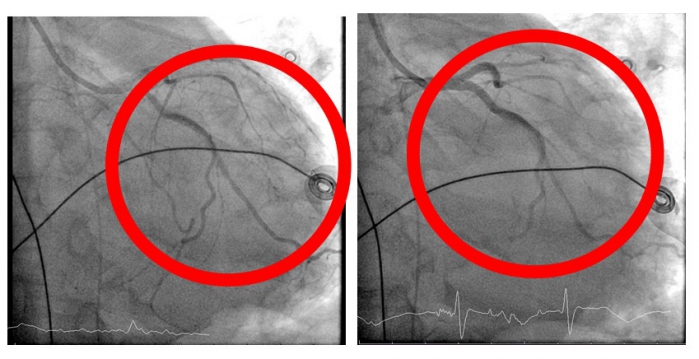

在葉克膜支持下,心臟內科張偉俊醫師立即安排緊急心導管檢查,歷時7小時完成高難度冠狀動脈鈣化旋磨與震波氣球治療(Rota-Shock策略),成功打通三條嚴重阻塞之冠狀動脈並完成支架置放,同步放置主動脈內氣球幫浦(IABP),以提升心臟輸出量、減輕心臟負荷並穩定血流動力。